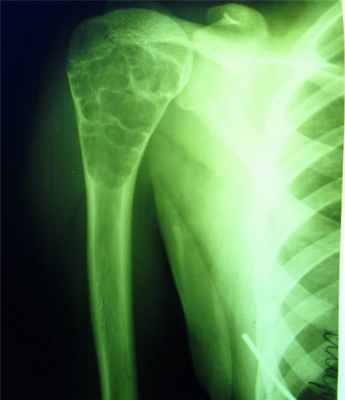

Остеохондрома

- кроме костной ткани содержит и хрящевую, покрывающую поверхность опухоли в виде шляпки,

- исходит из плечевой кости, из мета-эпифизов в области коленного сустава, в головке малоберцовой кости, грудной отдел позвоночника(исходит из дужек или отростков),

- опухоль сидит на широкой ножке и возвышается на кости в виде цветной капусты.

- поверхность ее бугристая, контуры резко очерчены,

- корковое вещество кости переходит на поверхность опухоли или выступает в середину нароста, рассыпаясь на отдельные костные прослойки, идущие в виде лучей к поверхности опухоли,

- рисунок ее не гомогенен, состоит из костных островков, веерообразных пучков и перегородок, лежащих среди светлого фона хряща,

- остеохондромы обладают высоким потенциалом озлокачествления.